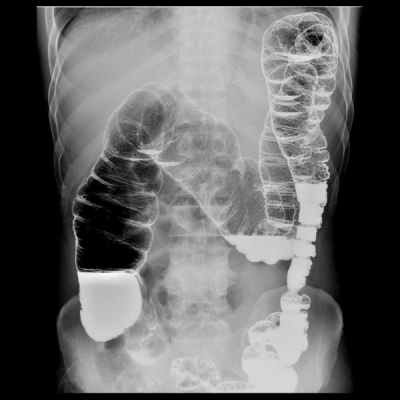

Различают несколько видов

рентгена толстого кишечника:

• ирригоскопию – процедуру, при

которой контраст вводится через

прямую кишку, ирригоскопию с

двойным контрастированием, когда

в кишку вводится также воздух

(либо иной инертный газ) под

давлением,

• ирригографию – рентгеновские

снимки толстого кишечника,

заполненного контрастом.